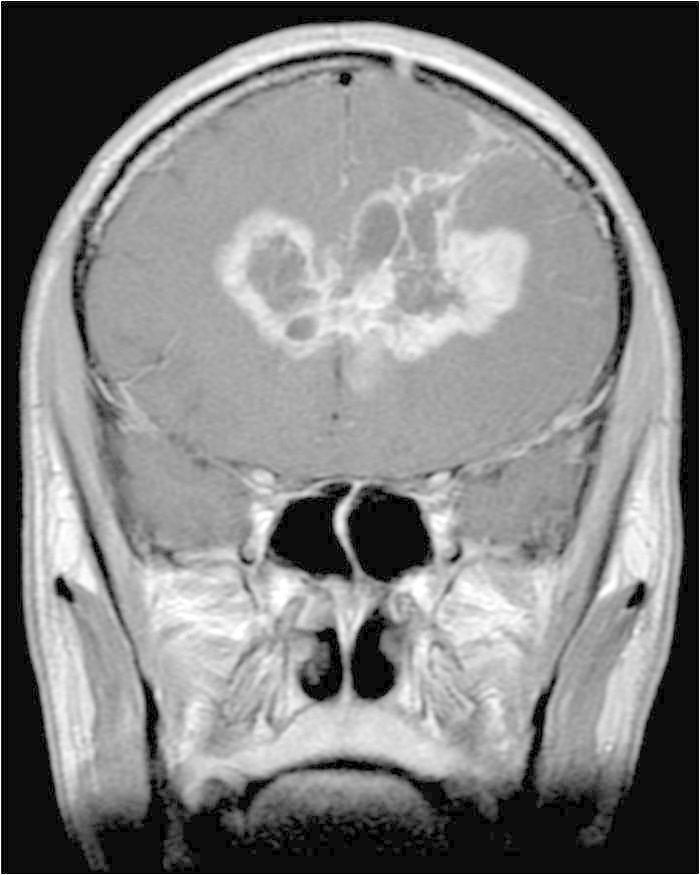

Classic butterfly appearance of glioblastoma multiforme

-butterfly w/ central necrosis